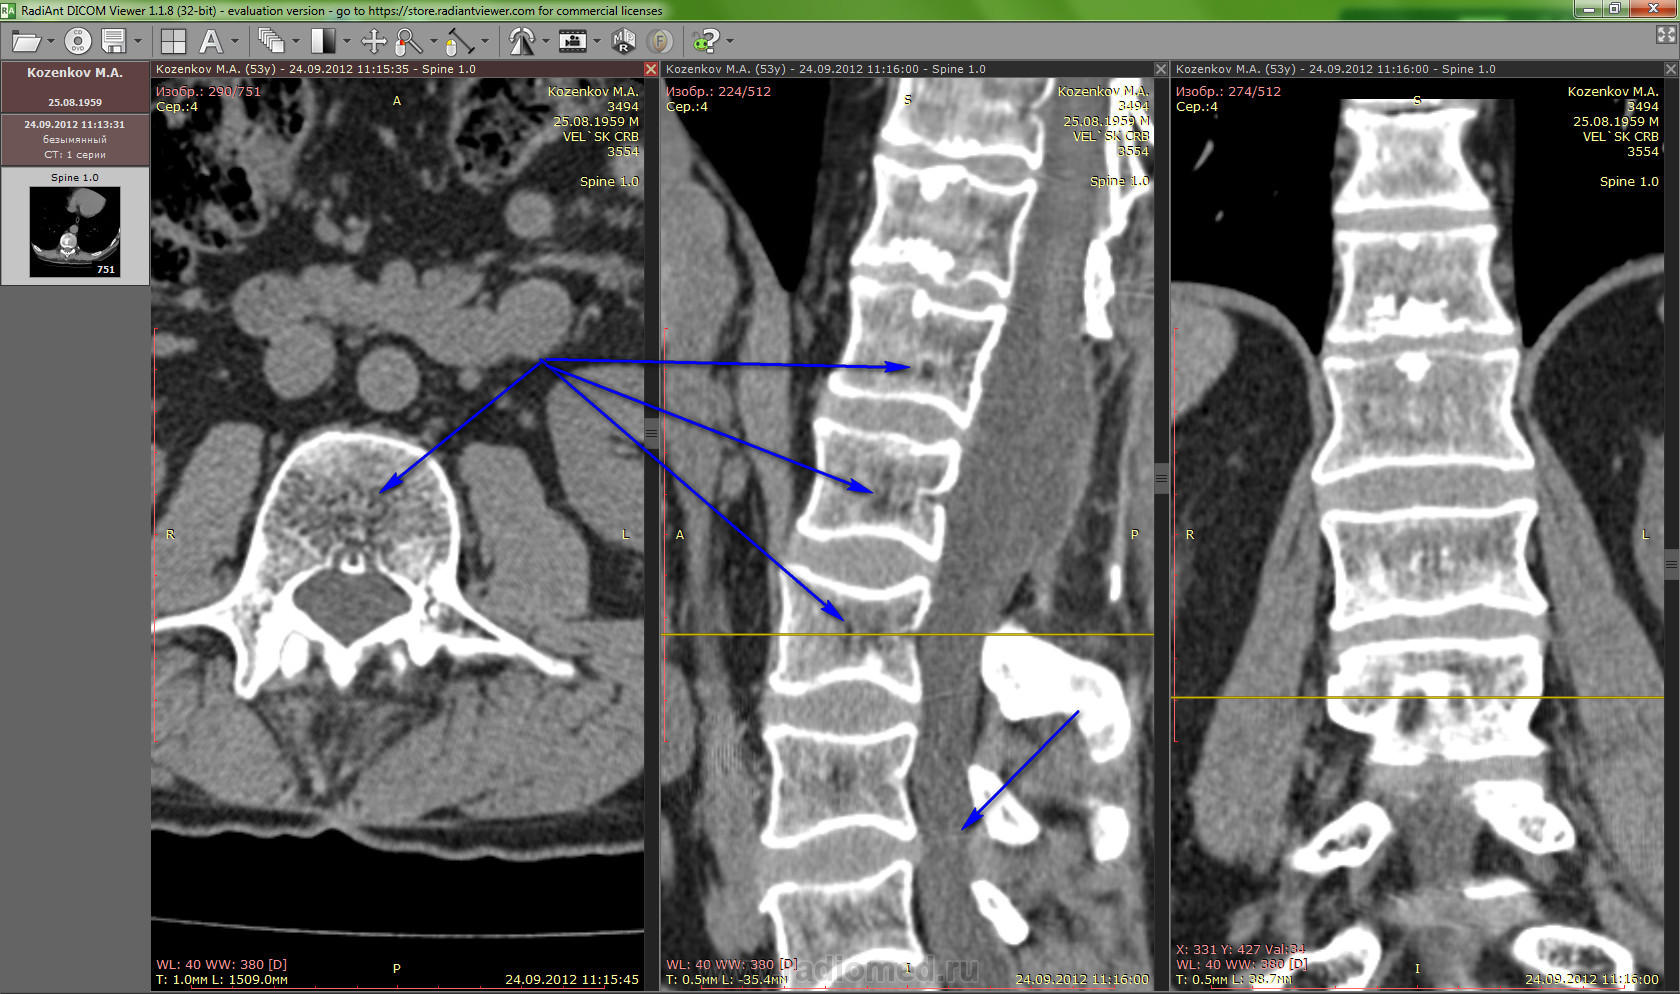

У меня просьба скажите , что это у меня еще с телами позвонков-как " кариес" ,и в районе L1-L2 за заплатой образование темное - что это?

Вот еще один снимок тут сдавливает спинной мозг и немеют ноги,и сильная боль, её не заглушить совсем ни чем, и не проходят сигналы стимулятора или еле слышу их.

Диагноз : Неоднократное удаление опухоли конского хвоста-псоматозная менингиома, арахноидит корешков конского хвоста, болевой нейропатический постламиэктомический синдром , имплантация нейростимулятора, пластика дурального мешка расширяющей заплатой, дегенеративные изменнения дисков грудного и поясничного отделапозвоночника, множественные грыжи Шморля.

"что это у меня еще с телами позвонков-как " кариес"

Венозные каналы тел позвонков.

"за заплатой образование темное - что это?"

Не очень ясно, но не опухоль, скорее жировая-фиброзная ткань.

"тут сдавливает спинной мозг и немеют ноги"

Ну мозга там нет, а "конский хвост" - да. И синдром "хвоста" очень болезненное дело.